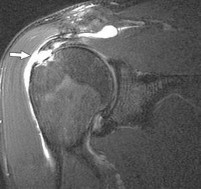

Phim cộng hưởng từ cho thấy các hình ảnh bệnh lý của CX, nó có độ nhạy và độ đặc hiệu lớn hơn 90% đặc biệt khi có tiêm thuốc tương phản từ.

Các dấu hiệu về bệnh lý gân CX trên phim có tiêm thuốc tương phản từ:

Rách bán phần gân: Trên phim thấy hình ảnh khuyết bề mặt gân cơ ở phía mặt khớp hoặc mặt bao hoạt dịch 50. Bao khớp không bị rách nên không thấy thoát thuốc đối quang ra ngoài ổ khớp.

Rách hoàn toàn gân: Thấy hình ảnh mất liên tục toàn bộ bề dầy gân cơ từ mặt khớp đến mặt bao hoạt dịch, nếu đứt hoàn toàn có dấu hiệu co rút cơ về phía nguyên ủy. Dấu hiệu gián tiếp trên CHT tiêm thuốc có thể thấy thoát thuốc đối quang ra ngoài bao hoạt dịch dưới MCV và dưới cơ Delta.

Hình 1.22. Rách hoàn toàn gân cơ trên gai 51